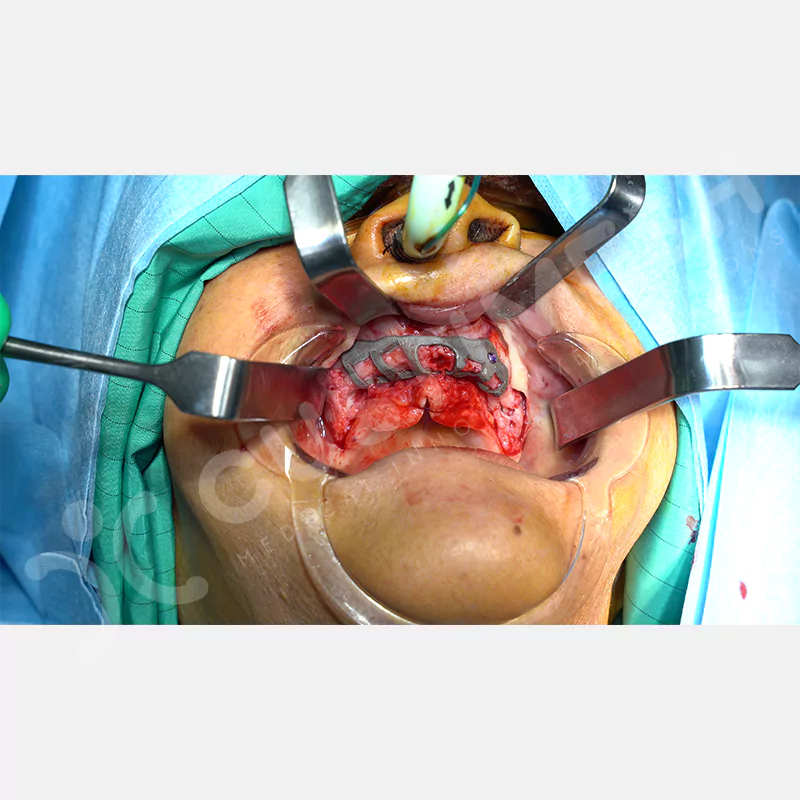

Modern diş hekimliğinde, çene gelişimini tamamlamamış veya ciddi kemik kaybı yaşayan hastalar için kişiye özel titanyum implantlar ile çözüm bulunmaktadır. CAD/CAM teknolojisi ve lazer sinterleme yöntemiyle üretilen bu implantlar, hastanın bireysel anatomik yapısına tam uyum sağlayarak geleneksel implantların uygulanamadığı vakalarda mükemmel bir alternatif oluşturmaktadır. Özellikle ileri derecede kemik kaybı olan hastalar için geliştirilen subperiosteal implantlar, periostun altına yerleştirilerek minimal invaziv bir yaklaşım sunarken, bilgisayarlı tomografi verileri ve sonlu eleman analizleriyle optimize edilmiş tasarımları sayesinde hem estetik hem de fonksiyonel sonuçlar garanti etmektedir. Bu yenilikçi teknoloji, tek seansta implant ve protez uygulamasına imkan vererek hastaların aynı gün doğal gülüşlerine kavuşmalarını sağlarken, kemik greftleme gibi ek işlem ihtiyacını ortadan kaldırarak cerrahi süreci büyük ölçüde kolaylaştırmaktadır. Kişiye özel tasarımı ve üstün biyouyumluluğu sayesinde, daha önce tedavisi mümkün görülmeyen kompleks vakalarda bile başarılı sonuçlar sunan bu implantlar, modern diş hekimliğinde yeni bir çağ açarak hastaların yaşam kalitesini artırmayı hedeflemektedir.

VAKA 1

VAKA 2

VAKA 3

VAKA 4